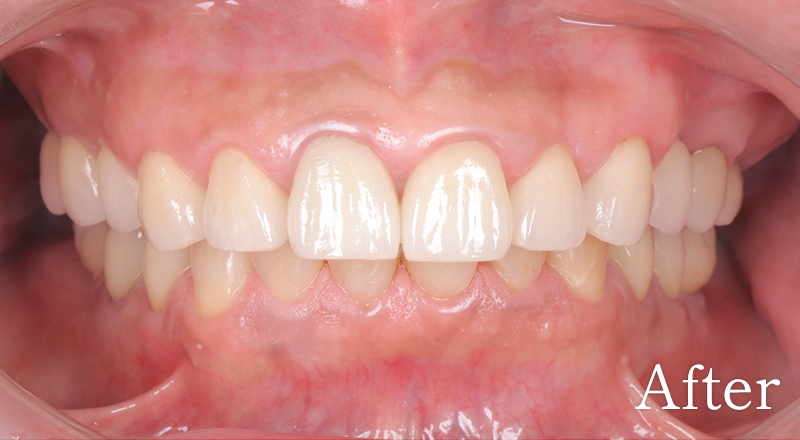

CASE4

骨格1級患者に対し、臼歯部にインプラント治療を行い咬合回復を行なった1症例

主訴 右側でうまく噛めない

治療内容 下顎臼歯部インプラント、咬合再構成、上顎矯正治療、セラミック治療

治療期間 約2年

費用 診断料:22万円(税込)

下顎顎臼歯部インプラント埋入手術:22万円(税込)×4本

セラミック補綴:22万円(税込)×4本

セラミック治療:11万円(税込)×9本

矯正治療:44万円(税込)